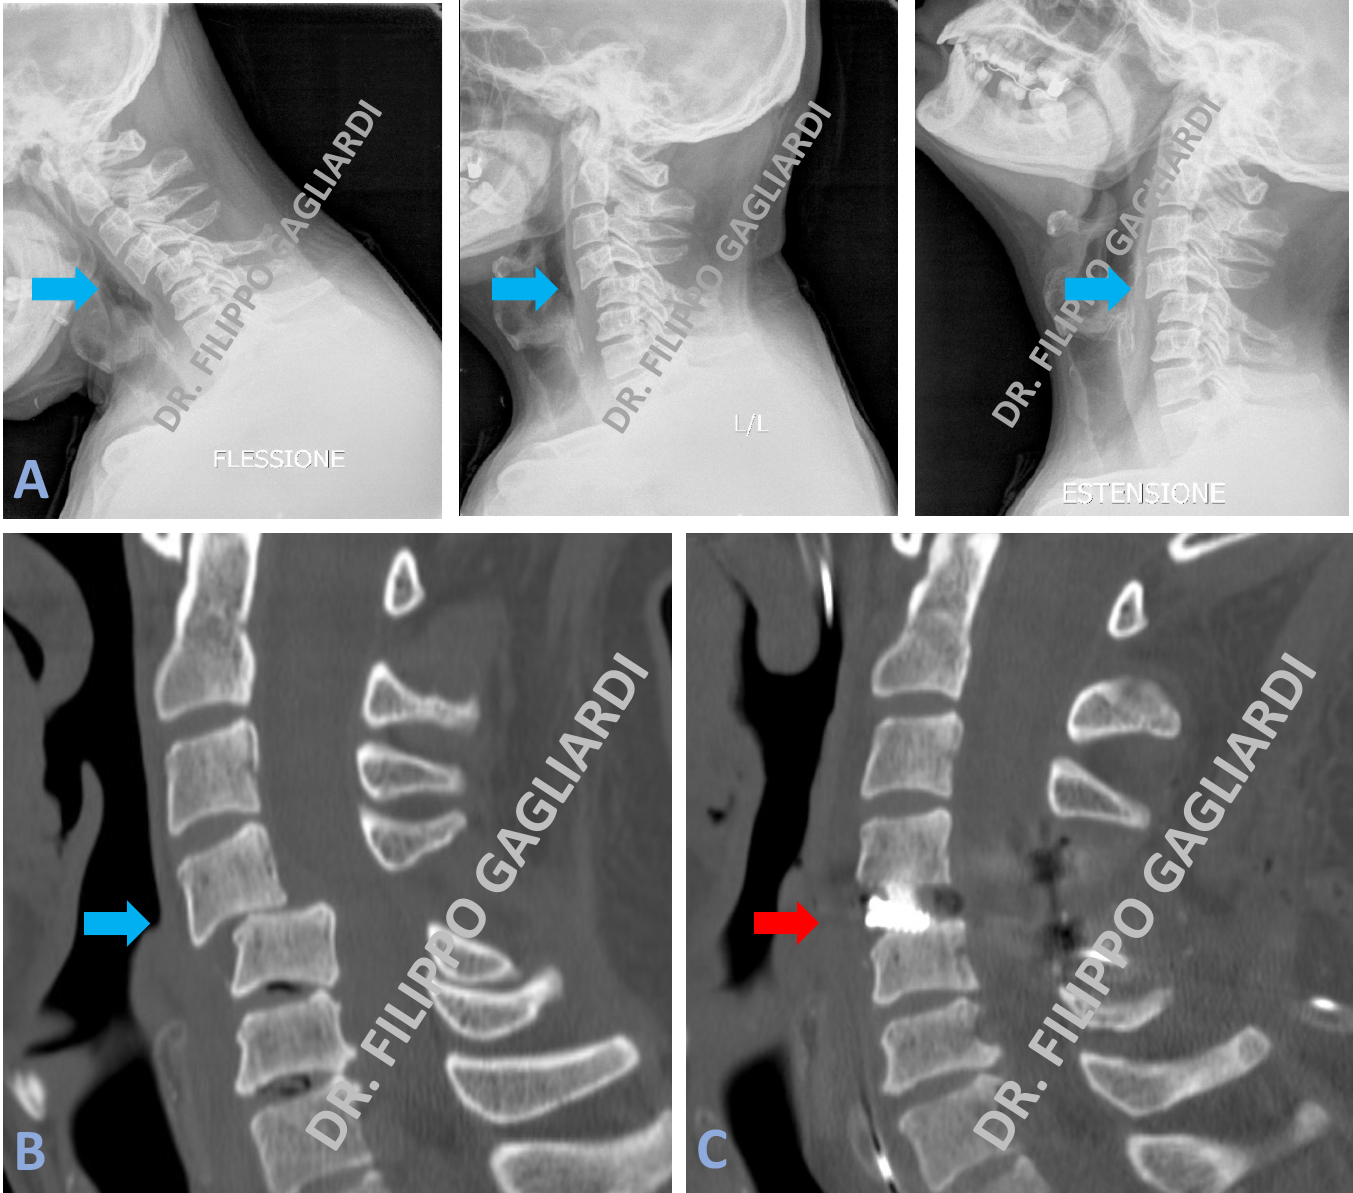

Stabilizzazione cervicale Caso di frattura pluri-frammentaria della prima vertebra cervicale (atlante) (frecce azzurre Figura A). La frattura è stata efficacemente ridotta in sala operatoria (frecce rosse Figura B) e stabilizzata con una intervento di fusione occipito-cervicale con un sistema di viti e barre posizionate a livello della seconda, terza e quarta vertebra cervicale e dell’osso occipitale (freccia rossa Figura C). La Figura A mostra la vertebra fratturata prima dell’intervento, le frecce azzurre mostrano le linee di frattura e il conseguente dislocamento dell’osso. Nella Figura B si vede la vertebra dopo l’intervento con la ricomposizione di tutti i frammenti fratturati. La Figura C mostra i controllo RX post-operatorio con l’impianto in sede.